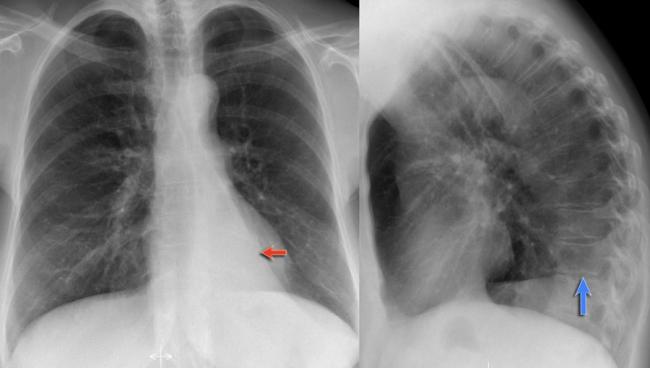

На рентгеновских снимках выявляют следующие признаки, указывающие на спадение легочной ткани:

Однородное затемнение в области поражения. Размеры тени зависят от вида ателектаза: при долевом выявляется обширное затемнение, при сегментарном — в виде клина или треугольника, расположенного вершиной к корню легкого, дольковые ателектазы множественные и похожи на очаговую пневмонию. Дистензионный ателектаз расположен низко, около диафрагмы, имеет небольшие размеры и вид поперечных полос или темных дисков. Смещение органов: при компрессионном ателектазе смещение наблюдается в здоровую сторону, так как на стороне поражения давление больше, при обтурационном, наоборот – смещение будет в сторону ателектаза, так как на стороне поражения нарастает притягивающее отрицательное давление. Подъем купола диафрагмы – это видно по расположению печени.

Помимо всего перечисленного выше, рентгеноскопия, то есть исследование «вживую», позволяет увидеть куда смещаются органы в зависимости от фазы дыхания, кашля. Это является дополнительным признаком ателектаза, помогающим выявить тип болезни.

Предварительным, рентгенологическим диагнозом является «синдром правой доли», при котором выявляется затемнение площади средней доли правого легкого.

Частое возникновение ателектаза правого легкого связано с анатомическими особенностями правого среднедолевого бронха: он узкий и длинный, поэтому часто происходит его перекрытие при патологическом процессе.